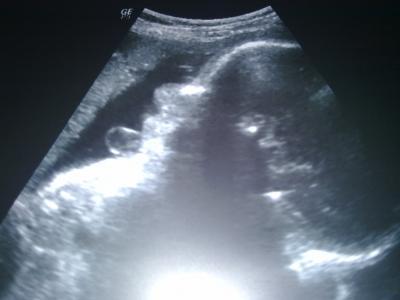

Sooo, bin wieder zurück von meiner VU (31+5). Es ist alles bestens, nur hat mich der US ein wenig geschockt... ET wurde plötzlich der 30.5. angezeigt (normal 13.6.) und alle Werte entsprechen mindestens der 34. bzw einer sogar der 35.SSW. Größe in etwa 44 cm, 2100 g, KU 30 cm... Der Doc meinte es kann sein dass es auch am vermessen liegt, kann aber auch sein dass es wirklich schon so groß ist und dann auch früher kommen würde. Darf nun schon in 2 Wochen wieder zur Wachstumskontrolle hin. Werte vom 2.Organscreening bei 30+0: 1470 g, 41 cm, KU 27 cm... LG Moni, die ab morgen nun auch endlich daheim ist...

Bild zu Zurück vom FA - Forum für Juni - Mamis

Wow, echt groß und ein schönes Bild!